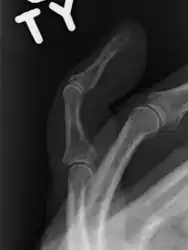

The diagnosis is generally based on symptoms and supported by X-rays.[3] The injury can be accompanied by swelling and ecchymosis.[6]

A mallet finger without an associated fracture